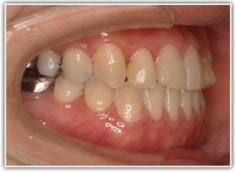

反対咬合ケース

治療法:表の矯正(T21ブラケット)

治療前